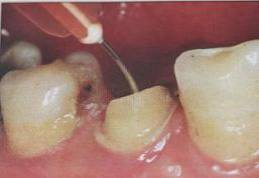

操作时:剪去纸尖尖部,插入根管,稍微加以压力,上下小幅度贴根管壁四周提拉,均匀吸收水分。当扁圆形根管时可使用两根大锥度牙胶尖。

根管内涂抹粘接剂的较规范操作应是:毛刷蘸取粘接剂在根管内反复涂擦20s,涂抹2-3层,然后用纸尖吸取干净,气枪吹5s使粘接剂中的溶剂快速挥发。此操作中,大锥度吸潮纸尖非常关键,它不仅可以吸取多余的粘接剂,同时也可使粘接剂在根管内铺展均匀。医生朋友不要“忽视小物件铸成大事件。